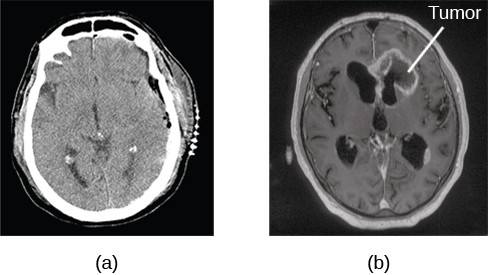

コンピュータ断層撮影computerized tomography(CT)スキャン

人の身体または脳の特定の部分に多数のX線を当てる。X線は、さまざまな密度の組織をさまざまな速度で通過するため、コンピューターはスキャン対象の体の領域の全体的な画像を作成できる。CTスキャンは、脳腫瘍の有無、脳萎縮の有無の確認に頻繁に使われる。